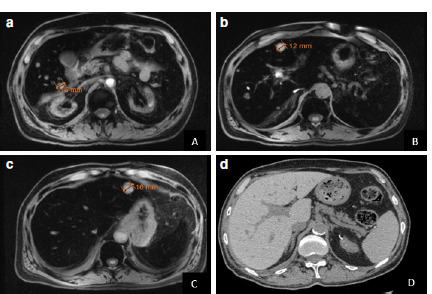

Yersinia pseudotuberculosis is a rare pathogenic organism in humans and is encountered mostly in patients with acquired or hereditary iron overload. This case report presents such a case with no known risk factors for iron overload, except heterozygous mutations in MPEG1 and HFE genes, while presenting the first patient with Y. pseudotuberculosis liver abscess in Turkiye. Here we present a 63-years-old male with known long-standing hypertension, type 2 diabetes, peripheral artery disease and chronic kidney disease presenting with right upper quadrant pain, nausea, vomiting and fever, whose imaging studies revealed multiple liver abscesses. While investigating the etiology, Yersinia pseudotuberculosis growth was observed in his abscess aspiration material and blood culture. Genetic analysis conducted after the detection of a ferritin level of 13725 µg/L, showed a heterozygous H63D mutation in HFE. Consequent whole-exon-sequencing reported an additional heterozygous p. Thr73Ala mutation in MPEG1. Even though, Y. pseudotuberculosis is detected mostly in patients with primary hemochromatosis, even heterozygous carriers of hemochromatosis may present clinically if concomitant comorbidities exist and may pose a challenge not only to clinicians but also to laboratory diagnosticians.